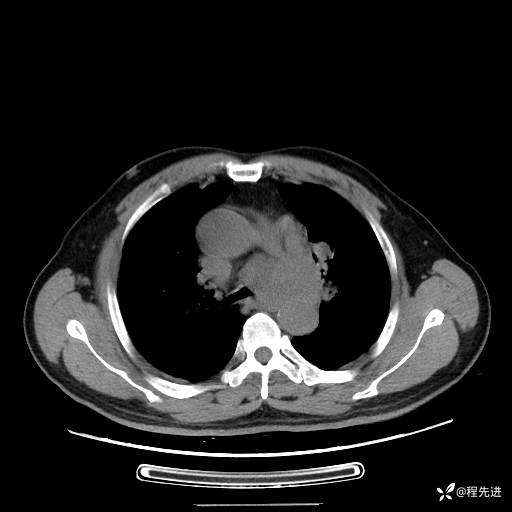

患者性别:男

患者年龄:57岁

简要病史:声嘶2月余

CT平扫+增强: